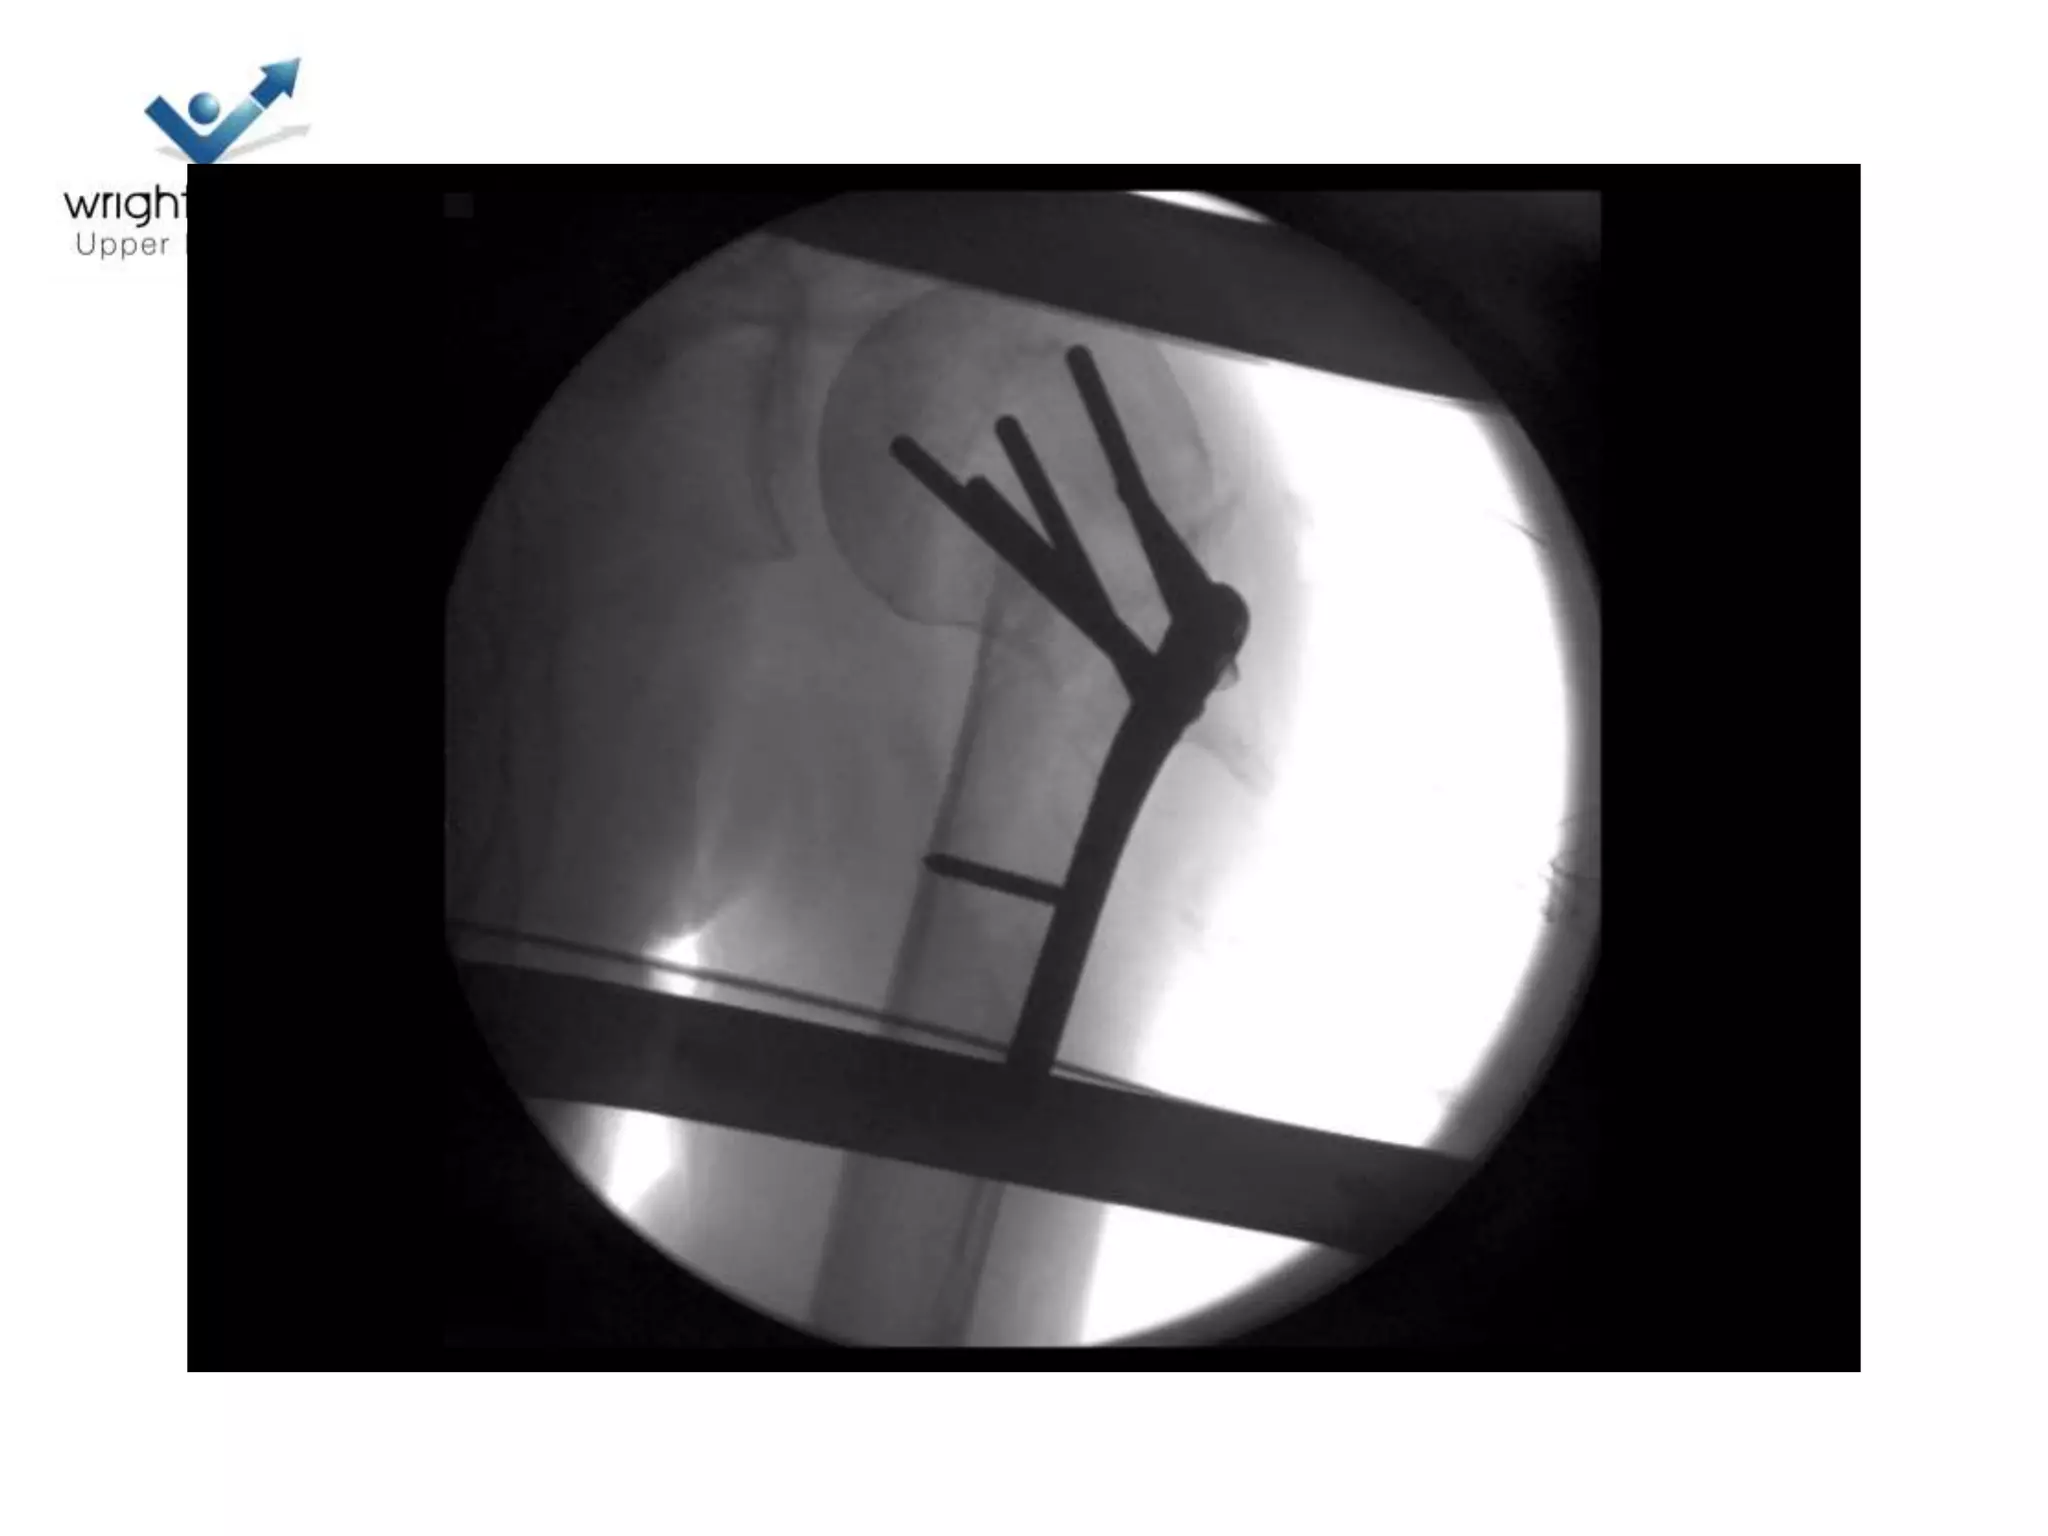

Locking plate; Tips

Locking plates: Tips

• Rotator cuff control

Images courtesy: AO

Locking plate: Tips

• Belts and braces

Prox humeral nail: top tip

Image Courtesy: AO